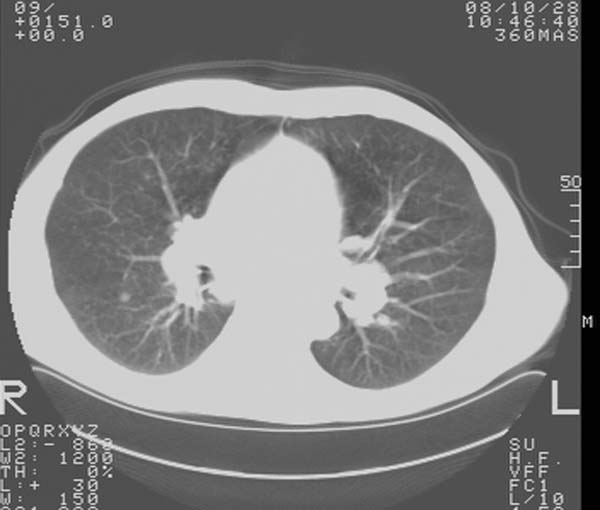

m,65y。半年前发现颈小结节,逐渐增多增大,现双侧耳后、颌下及颈部表浅淋巴肿大。胸片示双肺门增大。外院曾穿刺诊断为淋巴结核。在我科作胸腹部ct,我们觉得外院病检有误。现将图像上传请战友讨论。

我们也是首先考虑淋巴瘤。只是外院病检报告是结核。让人迷惑。肝左叶多发低密度占位,没增强不好定论。

现有资料不能明确!建议行强化及高分辨扫描。胸膜下可见小结节灶。分析思路:按可能性排序:结节病,淋巴瘤,结核。

纵隔内,双肺门、腋窝及腹膜后多发肿大淋巴结影,肺内小结节影,肝脾体积增大,支持淋巴瘤。肝内多发低密度影,考虑小囊肿。

最好做浅表淋巴结穿刺活检确定,结合实验室检查。